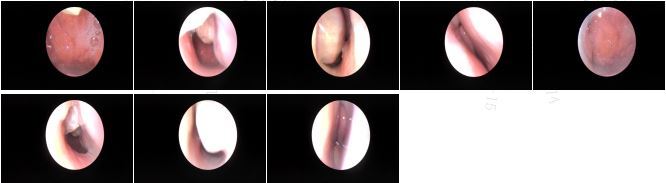

治疗前左侧鼻塞流涕3月入院,电子鼻咽镜和CT发现鼻腔内发现鼻腔鼻窦内有肿物,并有霉菌团块信号影治疗后治疗后150天术中证实鼻窦内翻性乳头状瘤和霉菌团块。术后鼻塞流涕症状消失,术后5月复查MRI鼻腔鼻窦肿瘤病灶完全清除,没有复发。